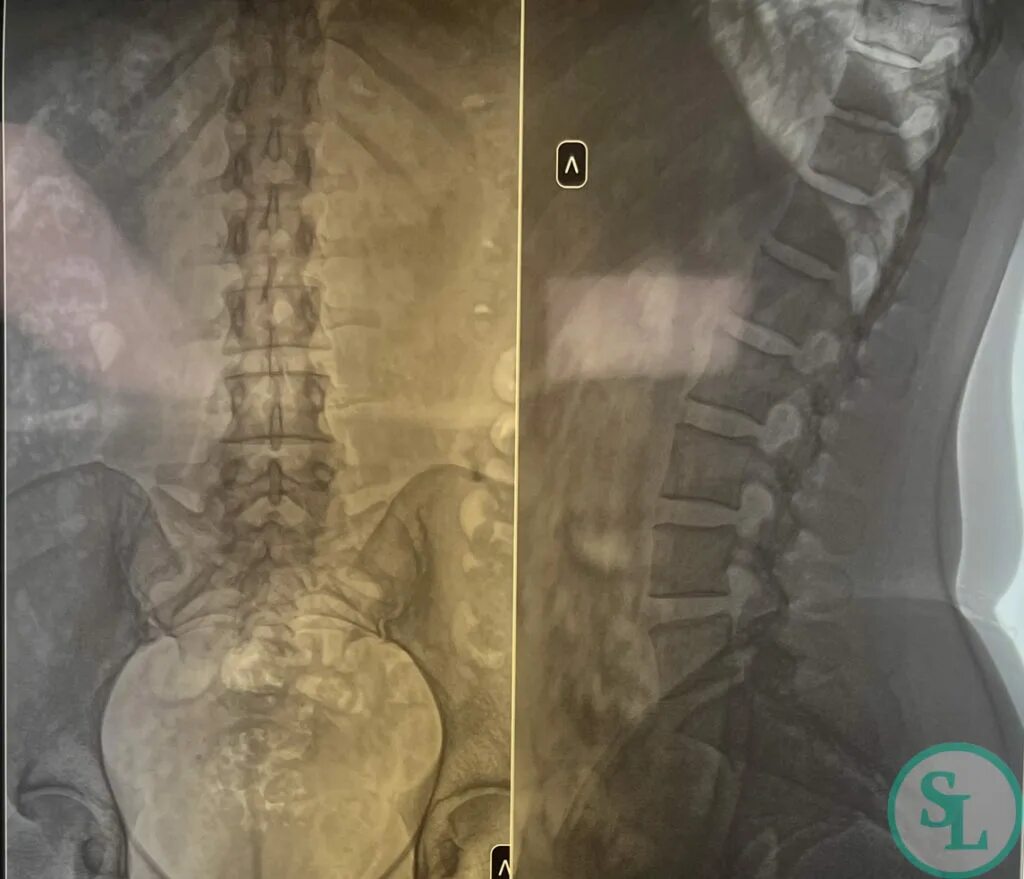

Остеохондроз l5 s1 дисков